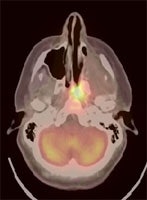

Recurrent head and neck cancer: The case below is from a 23 year old female with moderately differentiated squamous cell carcinoma of the left ethmoid sinus. Following pre-operative chemo and radiation therapy, residual tumor was surgically removed. Four months later a PET/CT exam showed local recurrence in the posterior nasal cavity and was also positive for cervical lymphadenopathy (not shown). The patient subsequently underwent a modified radical neck dissection, nasal endoscopy, and endoscopic tumor excision. Fusion images such as these shown below provide the greatest degree of anatomic correlation with the metabolic information derived from the FDG PET exam. Case courtesy University of Pittsburgh and CTI PET Systems, Inc. |